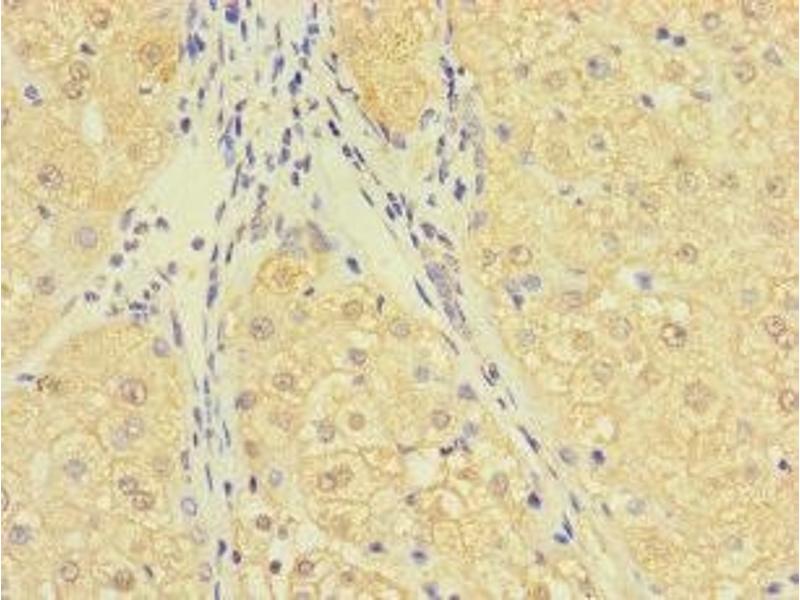

C10ORF111 抗体 (AA 1-114)

Quick Overview for C10ORF111 抗体 (AA 1-114) (ABIN7174695)

应用范围

- C10orf111 Antibody

- Recombinant Human Uncharacterized protein C10orf111 protein (1-114AA)

- C10orf111Uncharacterized protein C10orf111 antibody